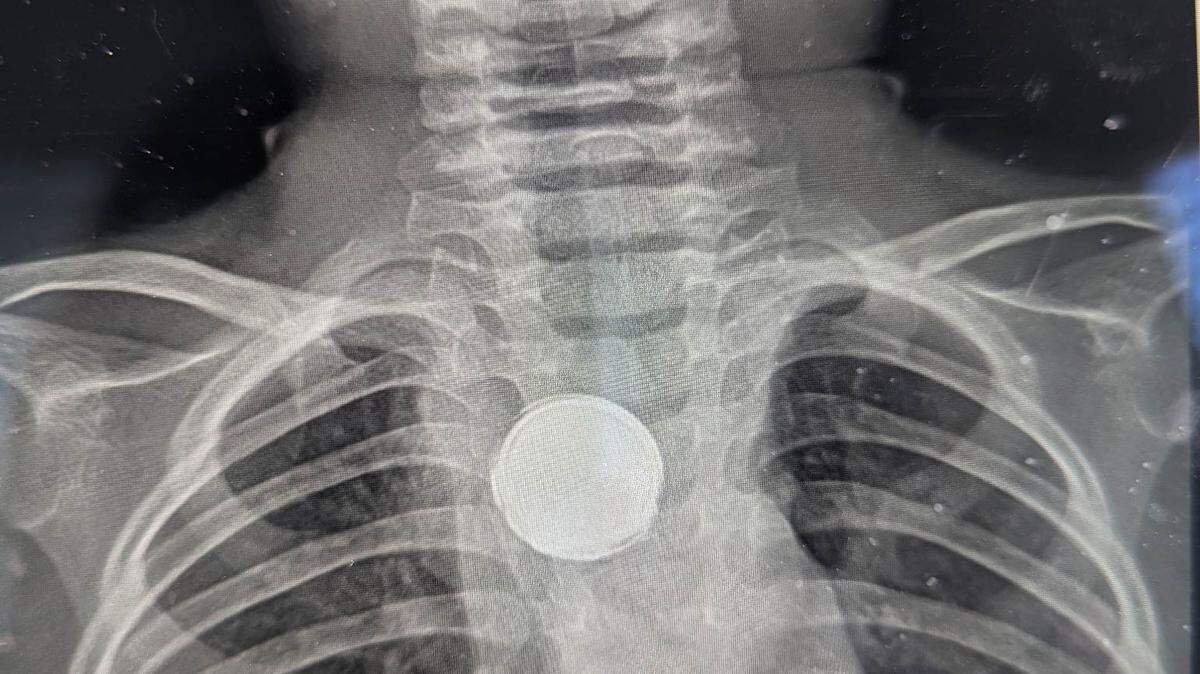

She took Luke to a different pediatrician, and this doctor ordered X-rays to take a look inside.

The doctors asked if Luke had a collar with a button or if he swallowed a coin. When his mother said no, Luke was rushed to the emergency room.

“(The doctors) were like, ‘there is no way it could be a battery because those … start corroding after just two hours,’” Erica McMillan said.

After a surgeon was called in to take a look, Erica McMillan said they told her there was something silver down there, but it was so stuck it would be dangerous to try to pull it out without a full team, in case something went wrong.

The surgeon told them they had found a lithium battery stuck to the inside of Luke’s esophagus, but it was wrapped in electrical tape, something that likely saved his life.